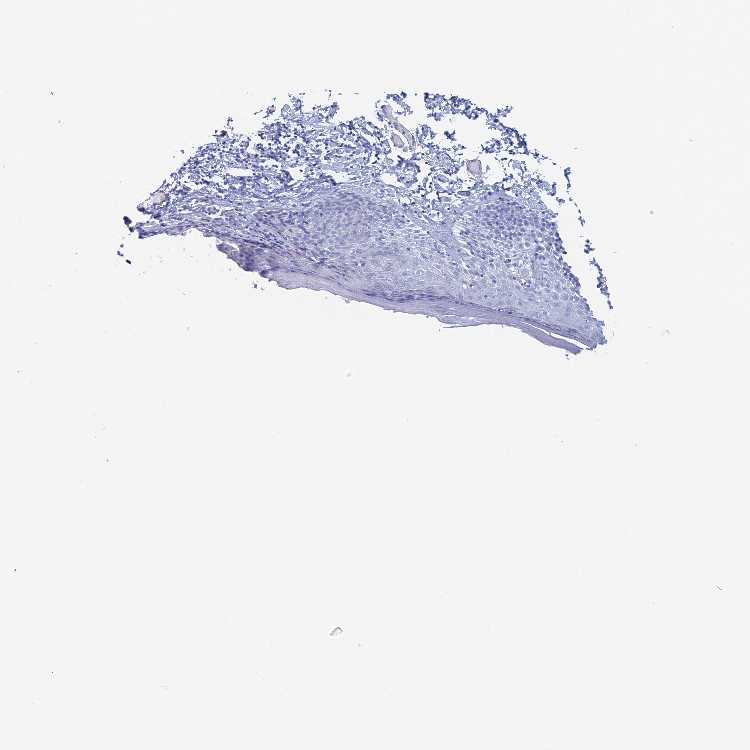

KCNK18